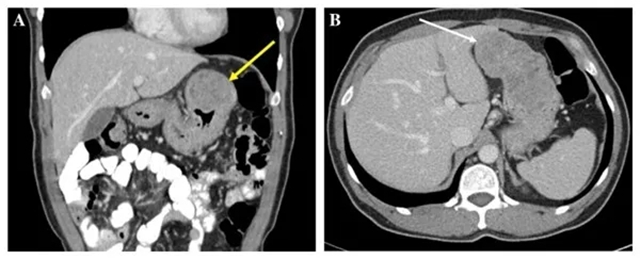

70岁的张大爷近来进食后老是觉得上腹部饱胀不适,便到医院进行体检,通过腹部CT发现左上腹有一个包块,怀疑是肿瘤,遂前往西南医科大学附属中医医院普外·疝与腹壁外科就诊,丁亮副教授完善相关检查后,为张大爷进行了手术切除治疗,术后病检证实:胃肠间质瘤!

此病的诊断多依赖于胃肠镜和CT、MRI、超声内镜等影像学检查。确诊具体的病理类型,尚需病理学检查及基因检测。